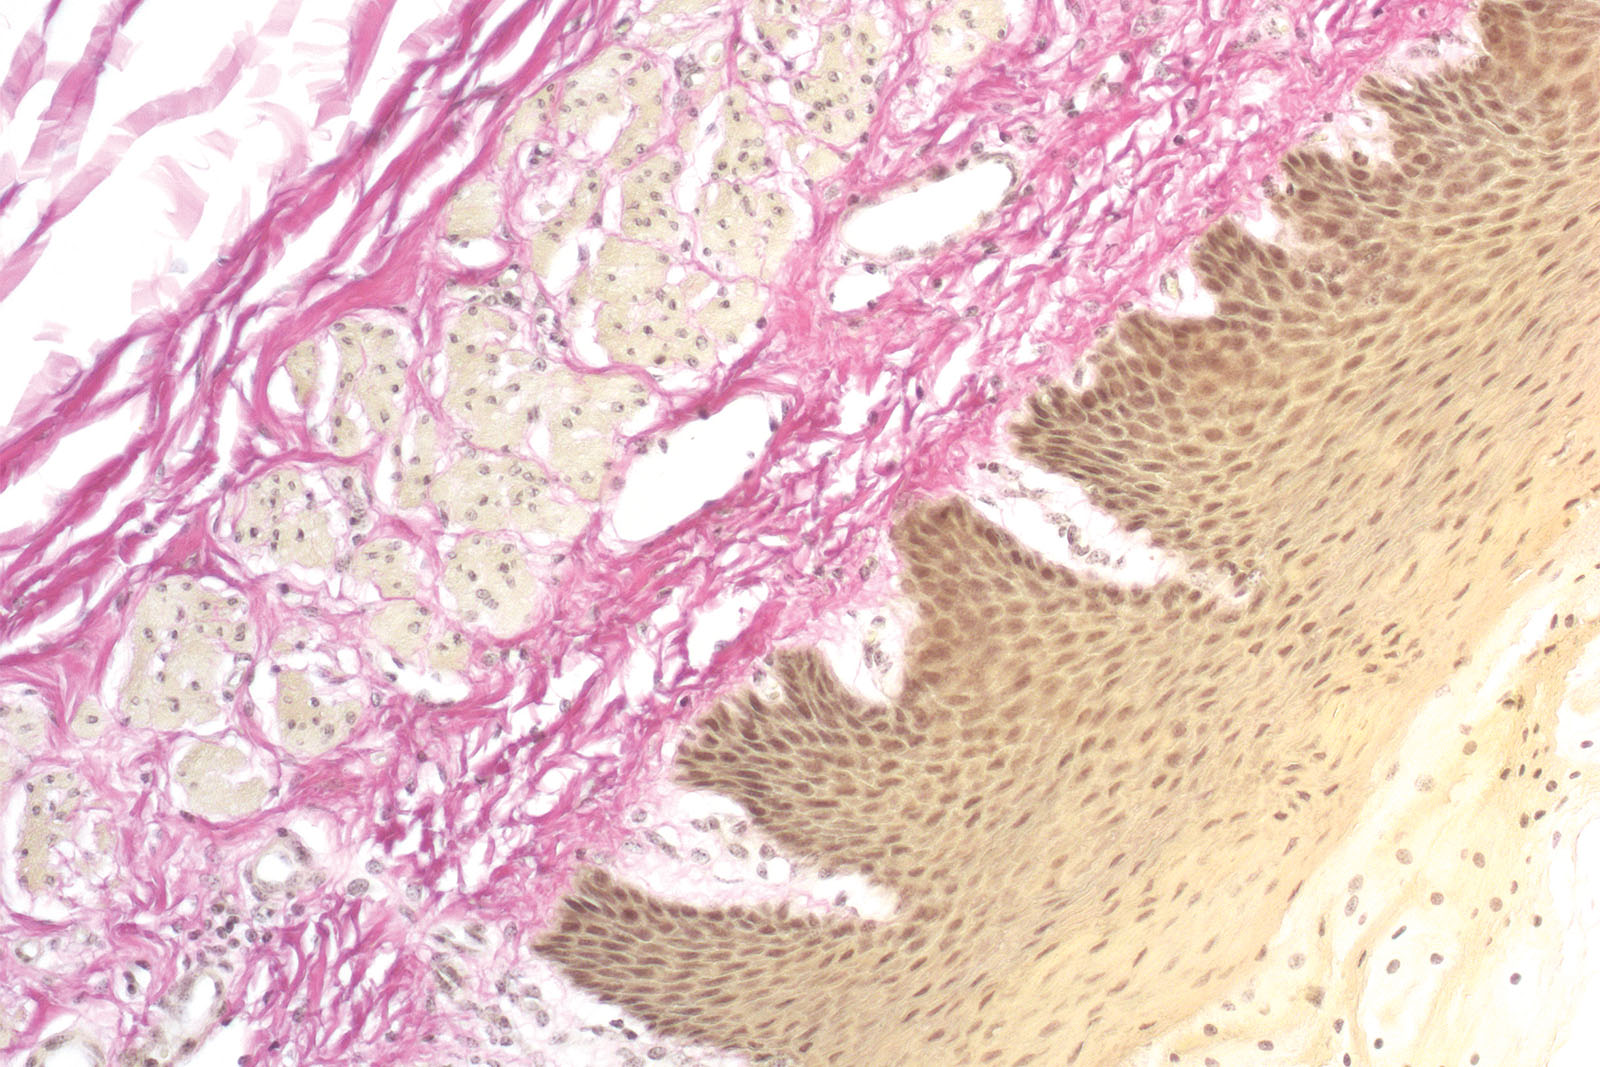

Van Gieson trichrome kit is used for staining collagen, muscle tissue, keratinized epithelium, cytoplasm, glial fibers, and erythrocytes. Fuchsin Acid Van Gieson is a component of the kit and it contains two dyes (acid fuchsin, picric acid) that simultaneously stain different tissue structures. Acid fuchsin stains collagen fibers intensive red while picric acid stains muscle fibers, erythrocytes and glial fibers yellow. Amyloids, hyalin, colloid and mucosa are stained in nuances between red and yellow. Hematoxylin, Weigert A and Ferri reagent make up Weigert hematoxylin that creates stable cellular nuclei coloration.